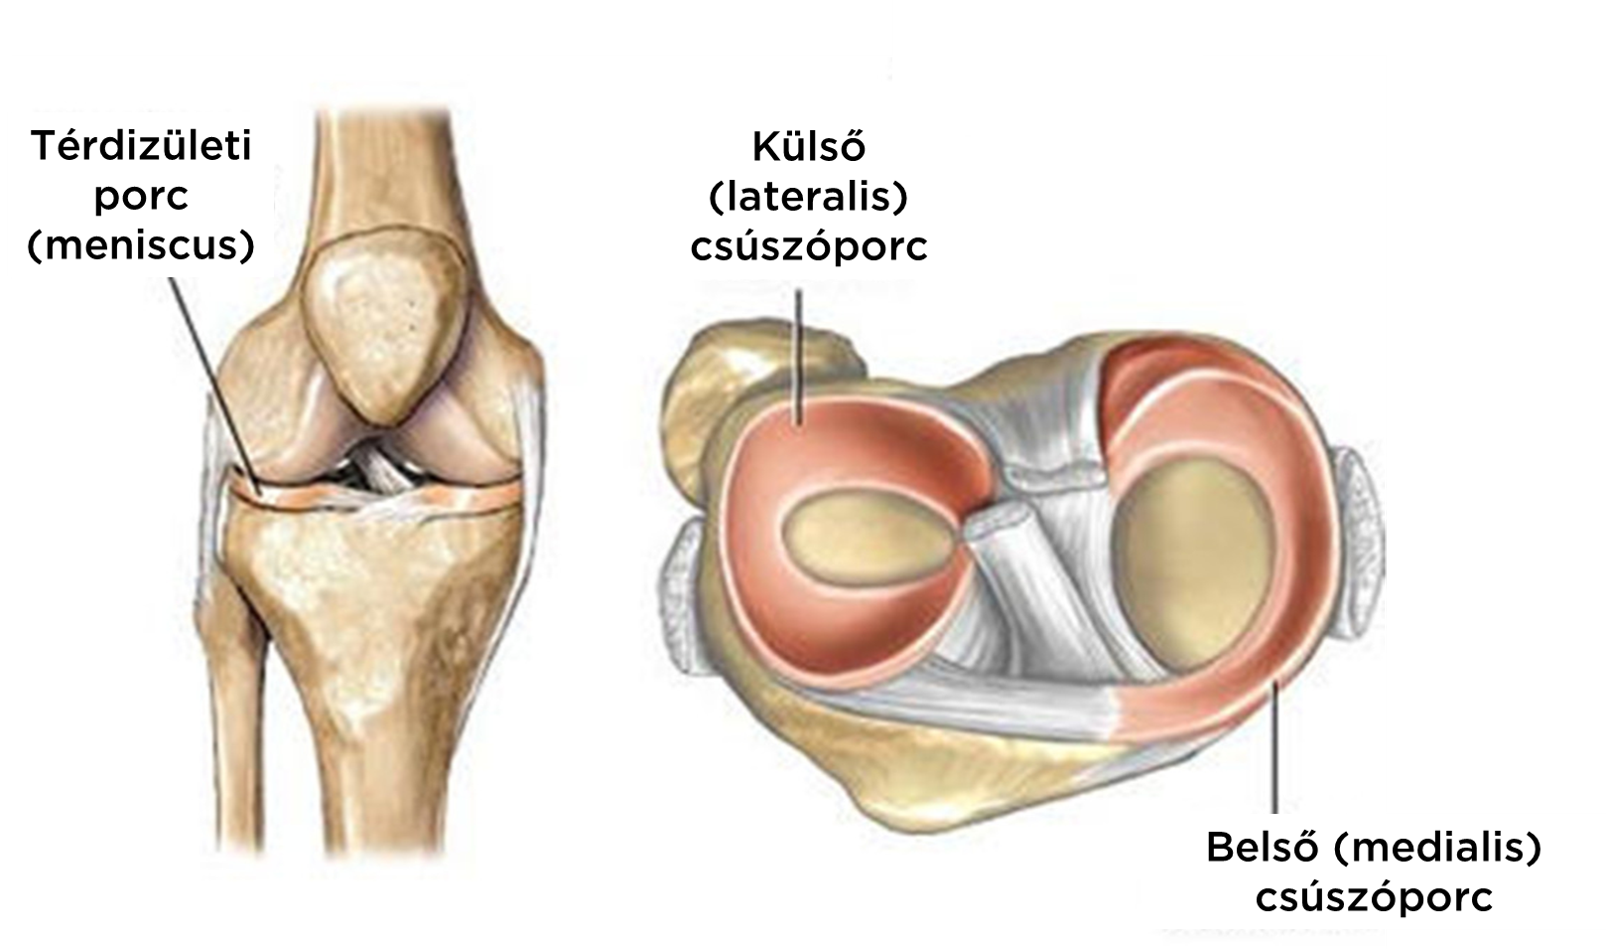

Проблемы с коленным суставом: флоттация и лечение